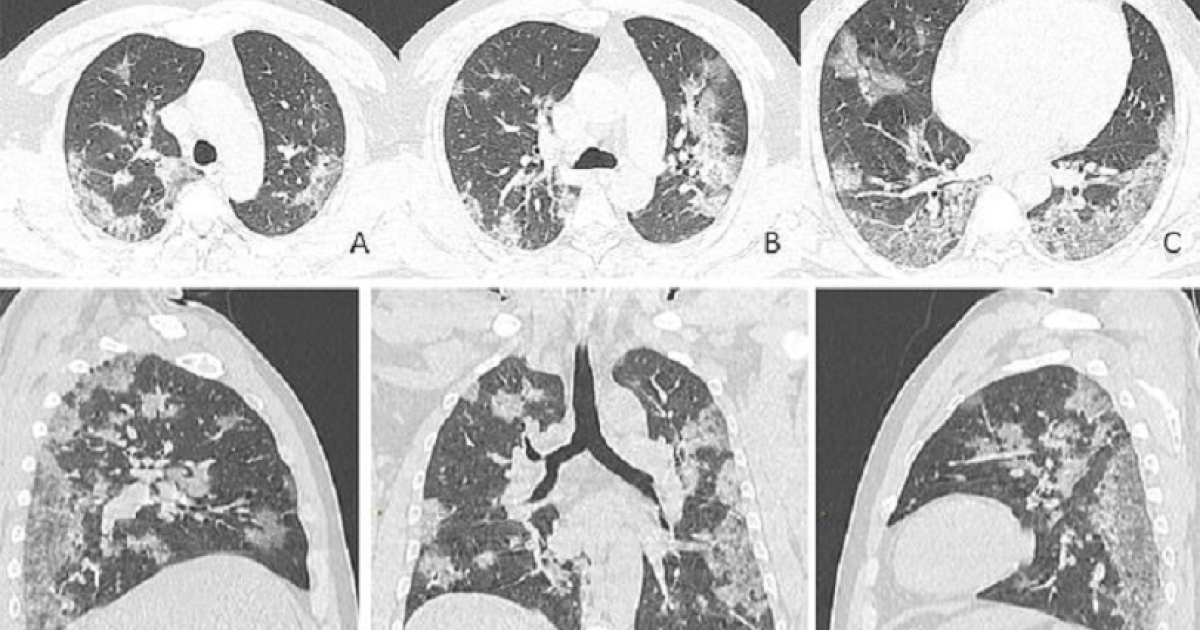

Σοκάρουν οι X-ray εικόνες και οι αξονικές τομογραφίες από τους πνεύμονες διαφόρων θυμάτων του κορονοϊού, συμπεριλαμβανομένων και εκείνων ενός 44χρονου Κινέζου από την Ουχάν, που πέθανε πριν από λίγο καιρό εξαιτίας του Covid-19.

Οι εικόνες δείχνουν λευκά «μπαλώματα» ή κηλίδες στις κάτω γωνίες των πνευμόνων, γεγονός που υποδηλώνει αυτό που οι ακτινολόγοι ονομάζουν ground glass opacity, δηλαδή, στα ελληνικά, σκίαση ή οζίδιο δίκην θαμβής υάλου (θαμπού γυαλιού), το οποίο συχνά αντιπροσωπεύει ένα αρχικό στάδιο κακοήθειας του πνεύμονα.

Η συγκλονιστική ακτινογραφία θώρακος ενός θύματος κοροναϊού, ενός 44χρονου άνδρα, που εργαζόταν στην ψαραγορά της Ουχάν, δείχνει αυτήν ακριβώς την ανωμαλία «θαμπού γυαλιού».

Στις εικόνες, που δόθηκαν στη δημοσιότητα από την Ακτινολογική Εταιρεία της Βόρειας Αμερικής (RSNA), μπορούμε να δούμε πόσο πιο έντονο γίνεται αυτό με την πάροδο του χρόνου. Κάντε τη σύγκριση, για παράδειγμα, της εικόνας Α με την εικόνα F. Η RSNA τονίζει στην ανάρτησή της πως είναι «διάχυτη η κατανομή βλαβών».

Ο 44χρονος άνδρας εισήχθη στο νοσοκομείο στις 25 Δεκεμβρίου 2019, αφού υπέφερε από πυρετό και βήχα για σχεδόν δύο εβδομάδες. Οι γιατροί διέγνωσαν τον άνθρωπο με πνευμονία και σύνδρομο οξείας αναπνευστικής δυσχέρειας. Παρά τη θεραπεία του από τους γιατρούς, πέθανε μια εβδομάδα αργότερα.